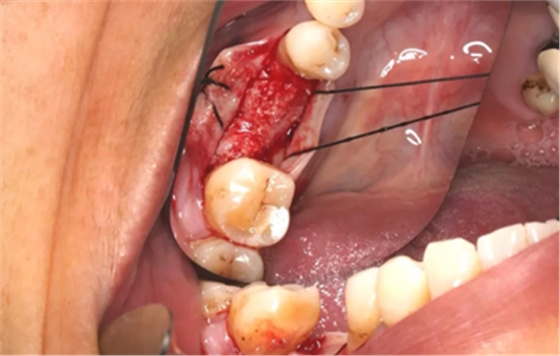

11、常规植入WEGO种植体一颗

牙槽嵴顶水平切口,翻瓣,牙槽嵴近中较远中丰满。

(摄于2017年4月14日)